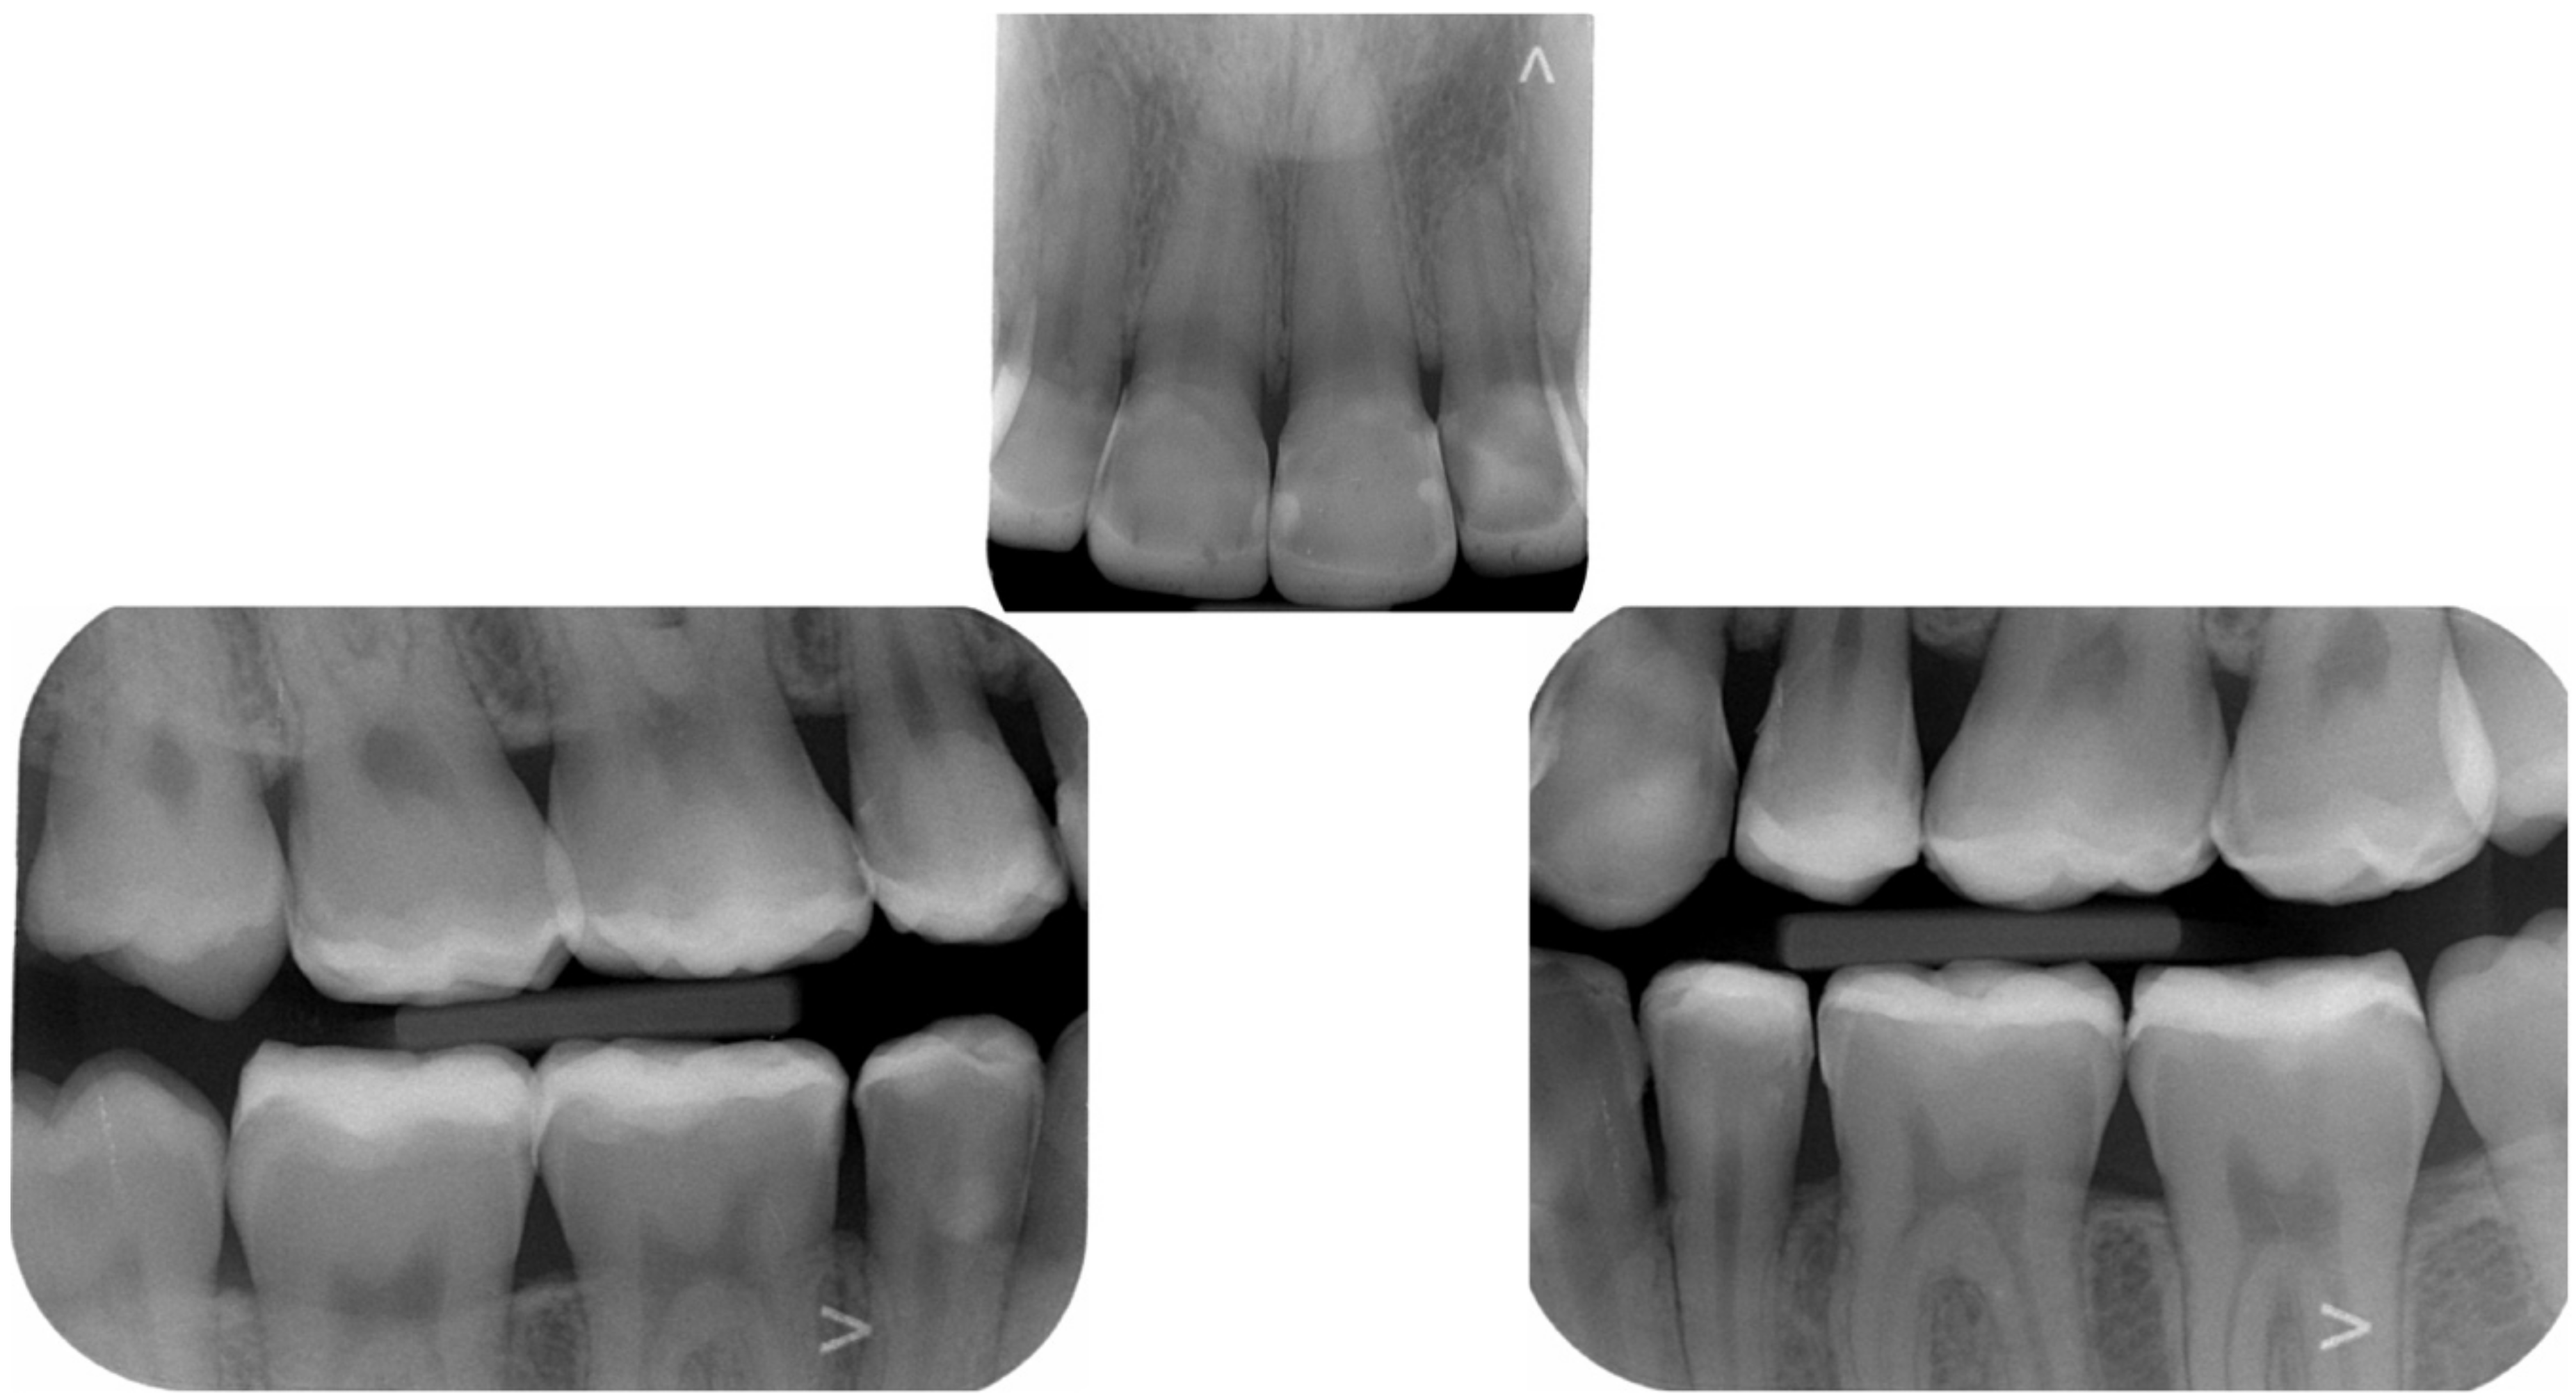

2.1. Planning Phase

2.2. Restorative Phase